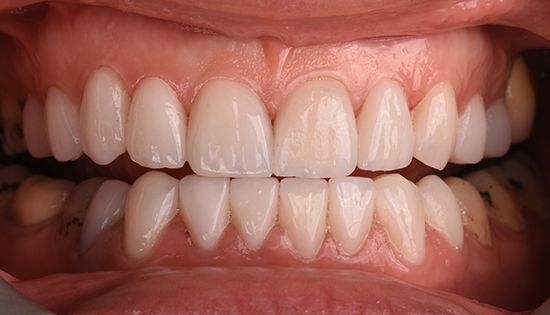

يلجأ الشخص إلى تحسين شكل أسنانه عن طريق فينير الأسنان أو ما يطلق عليه (عدسات الأسنان اللاصقة) وهي عبارة قشرة رقيقه يتم لصقها على السطح الخارجي للأسنان مصنوعة من مواد صلبة ذات معامل شفافيه مطابق للأسنان الطبيعيه   لعلاج مشكلة الاصفرار أو عدم التساوي والعديد من المشاكل الأخرى، حتى يحصل الشخص على ابتسامة رائعة تشبه ابتسامة نجوم هوليود.

• إظهار الأسنان بشكل أكثر جمالًا بعد تغطية كل عيوب الاسنان.